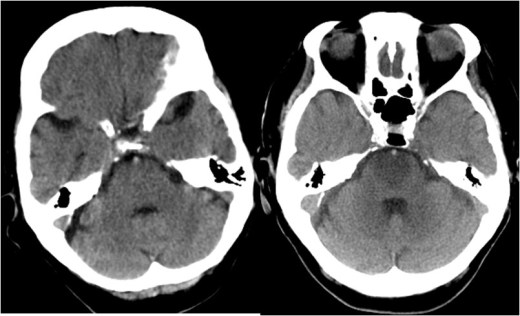

SIGNO DE LA ARTERIA BASILAR HIPERDENSA

Es un signo precoz de infarto por obstrucción por trombo o émbolo de la arteria basilar. El significado de la imagen es el mismo que el de la arteria cerebral media hiperdensa. Sin embargo es un hallazgo mucho menos común, menos reconocible, y cuya sensibilidad y especificidad no se ha determinado, a diferencia del signo de la arteria cerebral media hiperdensa.

La dificultad en reconocerlo estriba en la menor resolución de la tomografía para la valoración de la fosa posterior, en el trayecto del vaso transversal al plano axial (visible en pocos cortes), en la falta de referencia contralateral, y en la menor frecuencia y conocimiento de este hallazgo. La realización de cortes finos y de reconstrucciones multiplanares puede ayudar a mejorar a identificar el signo.

El caso que presentamos muestra el signo el signo en el estudio inicial del paciente (a la izquierda) y el infarto en la protuberancia en un nuevo estudio realizado a las 12 horas.

La obstrucción de la arteria basilar puede provocar un cuadro con un pésimo pronóstico ya que la mortalidad supera el 90 % de casos.